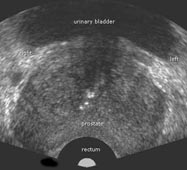

Der Prostatakrebs ist die häufigste bösartige Tumorerkrankung bei Männern.

Diese Erkrankung stellt außerdem die häufigste Todesursache infolge bösartiger Tumore bei Männern dar.

Die rechtzeitige Früherkennung und Behandlung des Prostatakrebses im Rahmen der urologischen Krebsvorsorge sind daher von allergrößter Bedeutung.